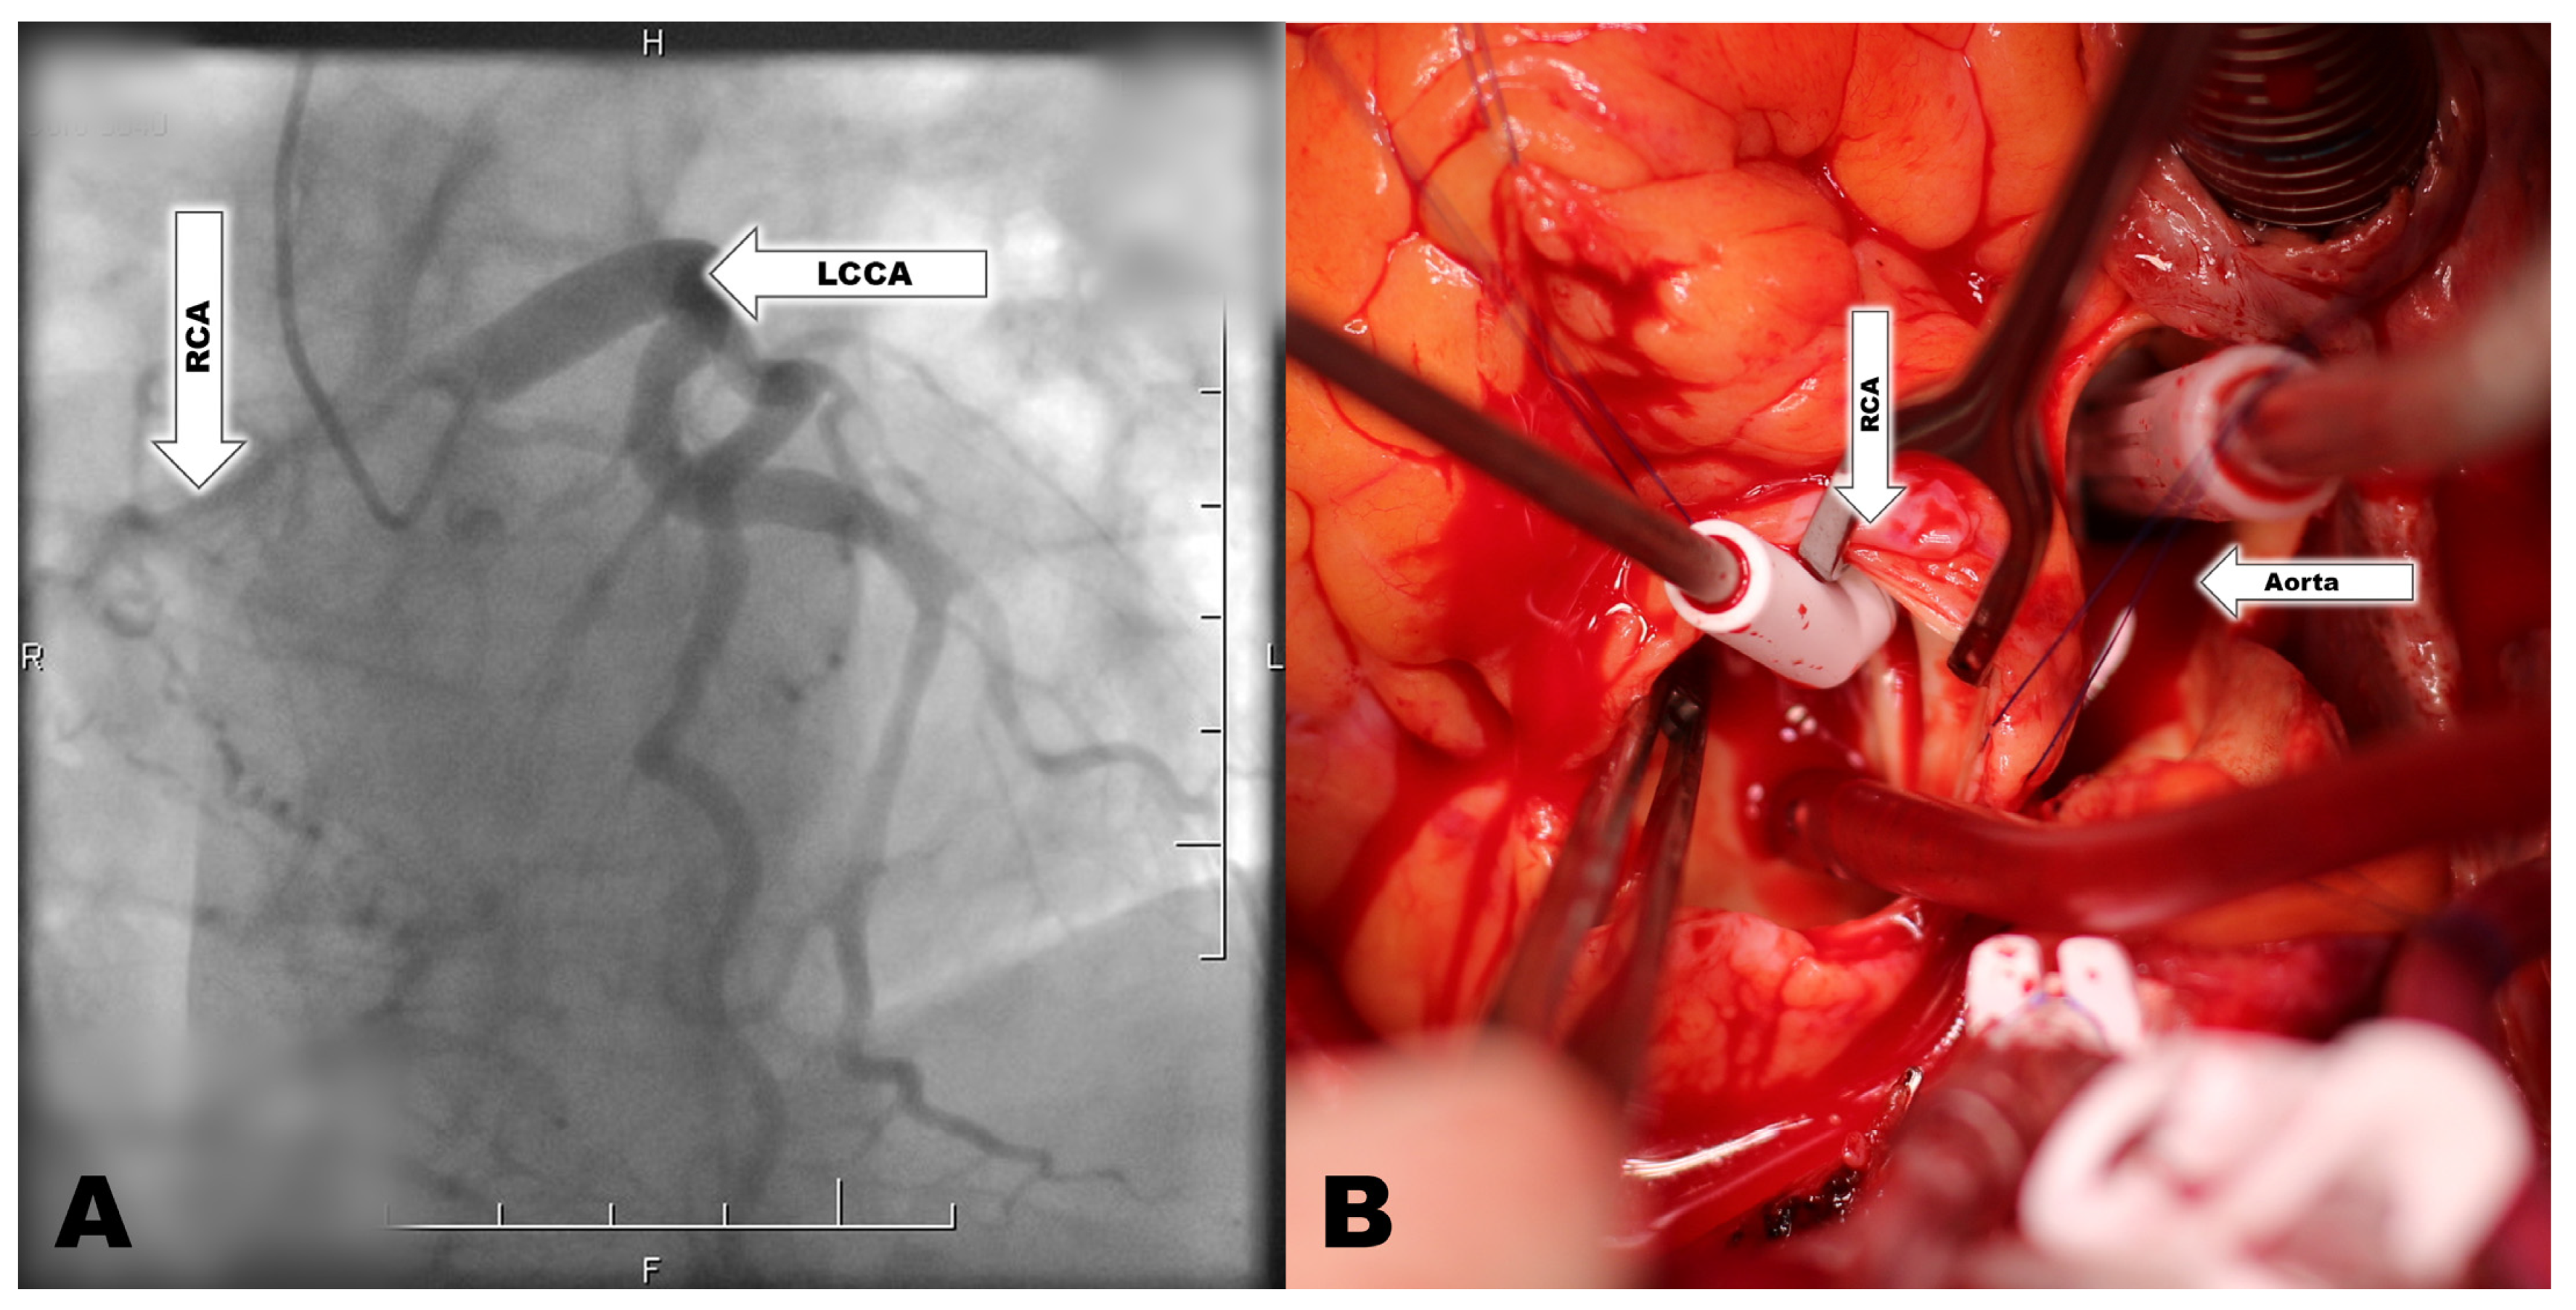

Anomalous Arising of Right Coronary Artery from the Pulmonary Artery

2. Case Report